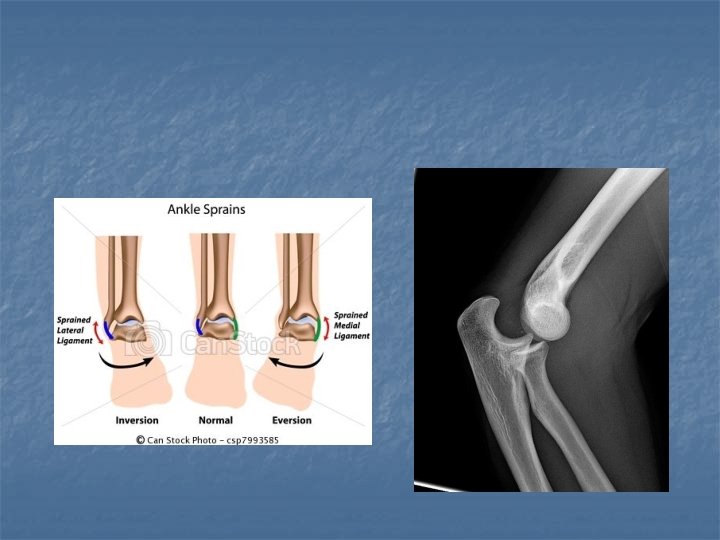

Bone Injuries n n n Fractures Dislocation Sprains

X-rays n n n Bones absorb x-rays and reflect image onto photographic film Used for bone injuries (breaks, dislocations) Provides clear images Can damage cells Cannot see soft tissue (muscle, organs)